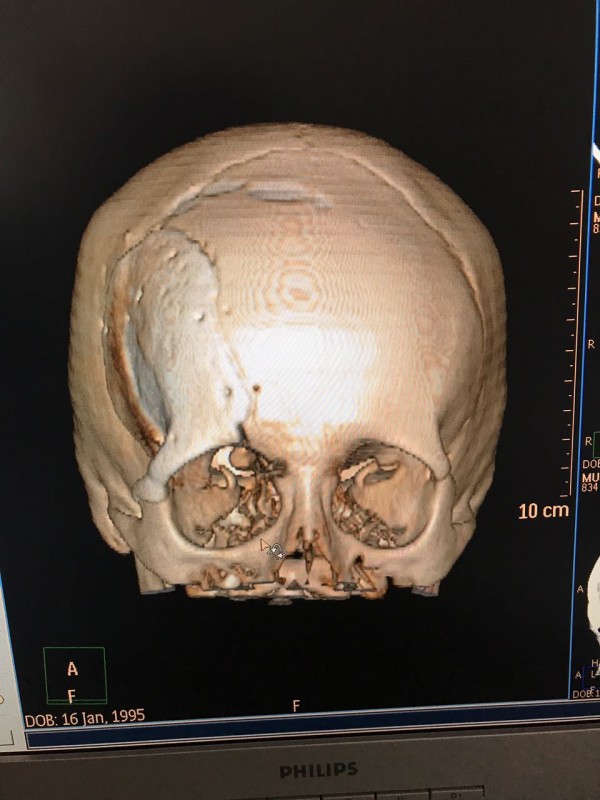

"Компьютерная томография показала, что костная опухоль поражала лобную кость и "крышу" орбиты глаза, которая, в свою очередь, сдавливала глазное яблоко. Чтобы убрать опухоль, потребовалось немало времени. Наша задача была сохранить глазное яблоко, зрительный нерв и сосуды. Если неправильно провести операцию и неправильно закрыть дефект, то в последующем это может привести к эстетической неполноте и асимметрии лица. Уникальность еще и в том, что в операции применялась 3D-стереолитография, которая делается только в Алматы", - рассказал он.

По словам нейрохирурга, операция заняла пять часов. Вначале врачи удалили опухоль, а потом в это место вставили специальную пластину, которая была изготовлена местной компанией. Технический директор ТОО "3D PM" Олег Лобах отметил, что в их практике это также был уникальный случай.

"Сначала на обычном 3D-принтере был напечатан образец из пластика. Потом мы опять смоделировали, напечатали на профессиональном принтере, там точность высокая. Толщина слоя - 10 микрон. Напечатанное отдается врачам, они стерилизуют, снимают силиконовую форму, ее тоже стерилизуют и уже она заполняется биоцементом (биосовместииый материал). Это считается готовый имплант. Он высыхает и идет на операцию, в череп человека. Для нас это уникальный и сложный случай, поскольку связано с глазными мышцами", - рассказал Лобах.